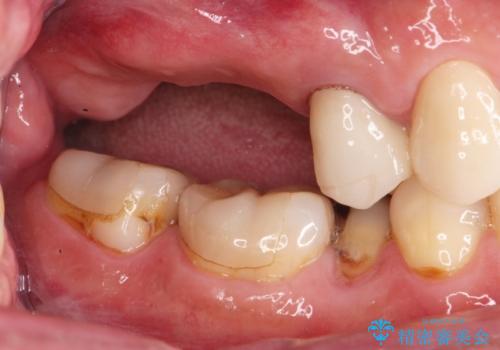

- 歯を抜いたまま放置してしまい、「やはりしっかりと噛めるような状態にしてほしい」とインプラント治療を希望され来院されました。

人工歯根であるインプラントを埋入することで奥歯でまたしっかりと噛める咬合機能を回復します。